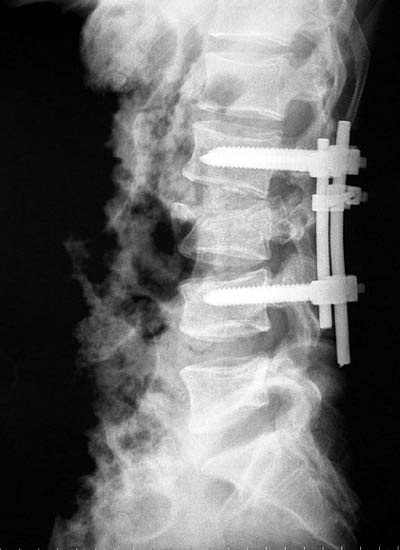

患者男性,30岁,腰3骨折,截瘫

CT显示腰3椎体爆裂,骨块凸入椎管压迫硬膜囊

施行后路椎管前方减压术及经椎弓根固定植骨术,彻底解除 脊髓前方的压迫及后凸畸形,截瘫部分恢复